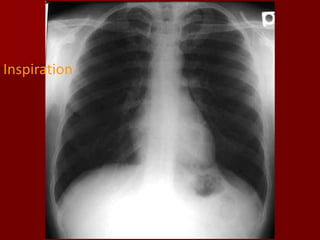

Inspiration:

The volume of air in the hemithorax will affect the

configuration of the heart in relation to cardiac size.

The vascular pattern in the lung fields will be

accentuated with a shallow inspiration.

The level of inspiration can be estimated by

counting ribs.

Visualization of nine posterior ribs, or seven

anterior ribs on an upright PA radiograph projecting

above the diaphragm would indicate a satisfactory

inspiration